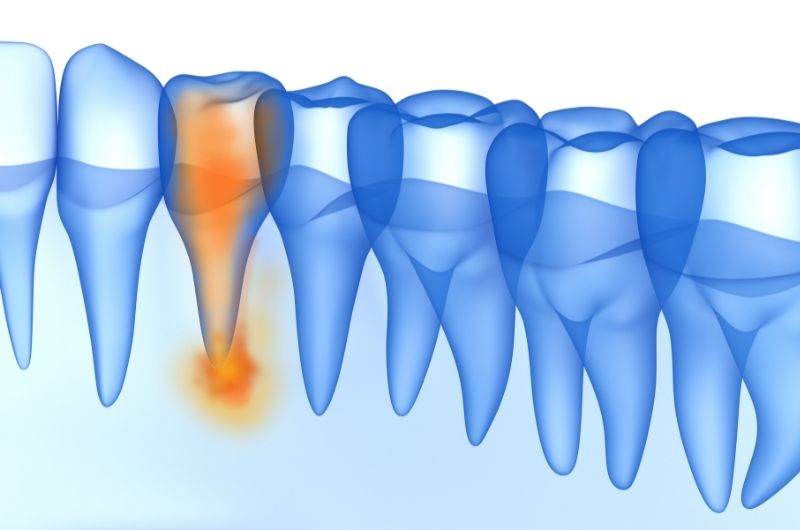

Fogbél gyulladásról akkor beszélünk, ha a fogbél (pulpa) gyullad be, amely a fog belső, idegekkel, erekkel átszőtt része. Kialakulhat a fogat ért trauma miatt vagy akkor, amikor egy kezeletlen fogszuvasodás már annyira mélyre hatol, hogy eléri a fog belső részét is. Köznyelvben ezt az állapotot szokták még foggyökér gyulladásnak is nevezni.

- Ha a szuvasodást ekkor nem kezelik, és a dentin is átlyukad, akkor a fertőzés eléri a fogbelet, a fogbél begyullad, a fájdalom állandóvá és hevessé válik.

- A fog körüli szövetek duzzanata, arc duzzanata (ilyen esetben már nem pusztán fogbélgyulladásról van szó. Ha az arc duzzanatát észleljük, az azt jelenti, hogy a fogbélben lévő gyulladás már annyira előrehaladott, hogy áttörte a gyökércsúcsot és a környező szövetekben okoz gyulladást. Ilyenkor már csonthártya gyulladásról beszélünk

- Ha a folyamat már visszafordíthatatlan, akkor a fogbél már nem menthető meg. Ebben az esetben gyökérkezelésre van szükség. Súlyos foggyökér gyulladás, vagy tályog kialakulása esetén pedig a gyökérkezelés mellett gyökércsúcs rezekcióra (a gyökércsúcs eltávolítása műtéti úton) is sor kerülhet. A cél mindenképpen a fog megmentése, az eredeti esztétikai és rágófunkció helyreállítása.

- Ha a genny nem tud távozni, súlyos esetben csonthártyagyulladás (periostitis), tályog vagy életveszélyes phlegmone (a gyulladás tovább terjed a kötőszöveti résekben) is kialakulhat